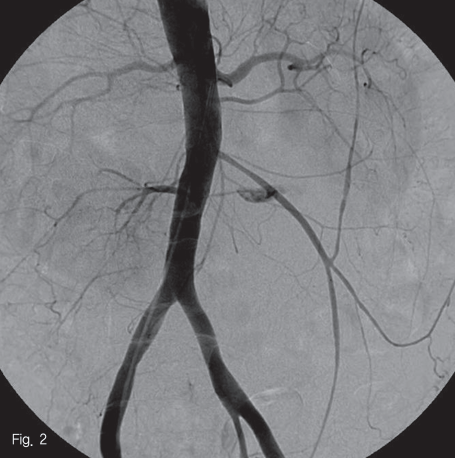

우측 대퇴동맥을 천자 후 5F straight catheter(Radifocus, Terumo, Tokyo, Japan)를 이용하여 시행한 대동맥 조영상 하부장간동맥 기시부 직하방에서 앞쪽으로 마제신의 양측 협부를 공급하는 좌,우 분지동맥이 공동동맥(common truck)을 이루고 있고 좌측 분지에서 현성 출혈로 판단되는 거짓동맥류가 있었다(Fig.2). 5F RH catheter(Cook, Bloomington, U.S.A)를 사용하여 공동동맥(common truck)를 선택하여 시행한 angiogram에서 좌측 분지에서 기원하는 거짓동맥류를 확인하였다(Fig.3).

Fig 2

Aortogram confirmed the presence of contrast filling sac(arrow) just below IMA, originated from left side branching artery from common trunk, supplying isthmic portion of horseshoe kidney.